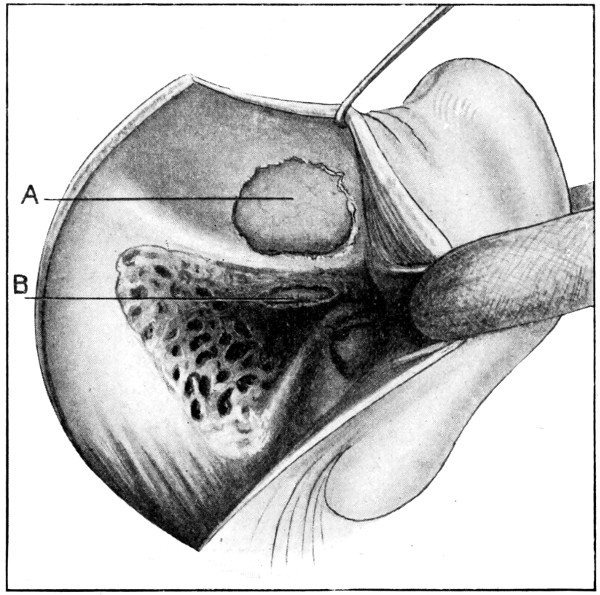

75. A large right-sided temporo-sphenoidal abscess 256

76. To illustrate the pressure effects of a temporo-sphenoidal abscess 257

77. A cerebellar abscess 259

78. To illustrate diagrammatically the symptoms observed in cerebellar abscess formation (after Luciani) 261

79. The exposure of a temporo-sphenoidal abscess 265

80. The ‘radical’ mastoid operation (after Hunter Tod) 269